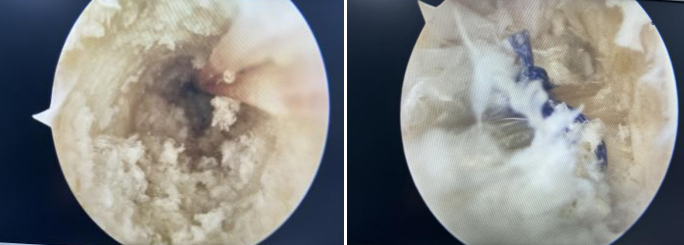

镜下见前交叉韧带完全断裂

取自体肌腱、编织肌腱

股骨、胫骨隧道重建